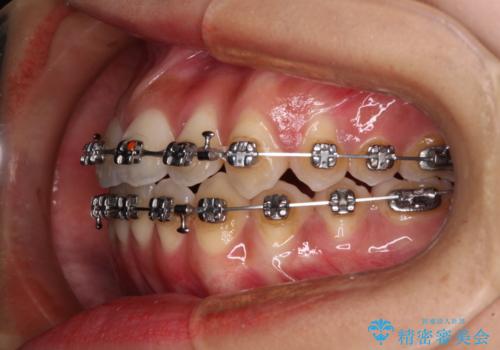

受け口と開咬を急速拡大装置とワイヤー装置で改善

- メタルブラケット

- 前歯の開咬と、受け口による咬み合わせの悪さを気にして来院された患者様です。

上顎歯列が狭窄していたため、急速拡大装置により上顎骨を側方に拡大し、その後ワイヤー装置にて矯正治療を行うこととしました。

舌の突出癖が開咬の原因であったので、改善のための舌トレーニングを行っていただきました。